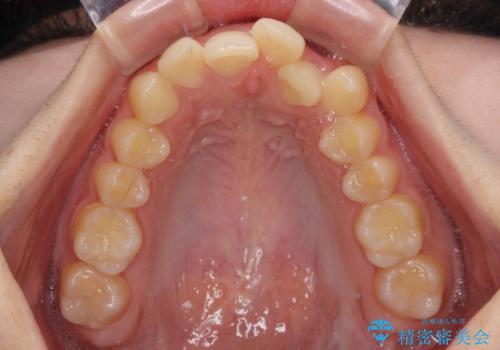

下顎の左右側切歯2本が欠損しており、上顎歯列がデコボコとなっている状態でした。

下顎歯列に対して上顎歯列が相対的に大きくなっているため、デコボコとなっているだけでなく、下顎前歯が見えなくなるくらいのディープバイトにもなっていました。

上顎左右第一小臼歯2本を抜歯し、ワイヤー装置にて矯正治療を行うこととしました。